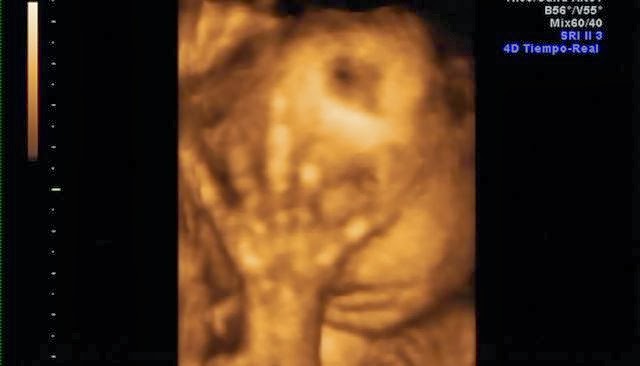

Su carita!Y estas son algunas capturas de pantalla de la eco 4d que me hice a principios de mes. Que ya de paso decir, que esta no me gustó NADA!! Tuvimos que esperar 2 horas para que nos cogieran, la eco nos la hicieron con prisas, y sólo se le vió la mitad de la cara.. así que para habernos gastado 100€ muy mal!! No os recomiendo la Ginecóloga de Gandia, Dra.Escrivá.

De momento parece que se parece a mami... jiji. Mi nariz, mi boca y mis mofletes :DEl padre se preguntó si era suyo.. jajaja, aunque tiene sus manazas.Y ahora os dejo unas fotitos de mi barriga en la playa, que aprovechando que esta semana aquí ha hecho muy buen tiempo nos hemos ido a hacernos un reportaje de fotos.